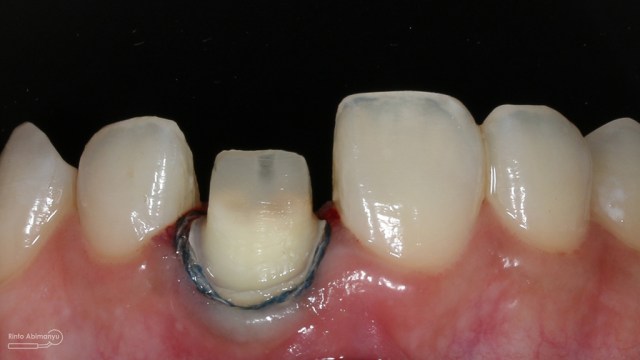

Untuk kunjungan pertama ini saya rencanakan melakukan perawatan saluran akar langsung pada dua gigi central… Saya pasang rubber dam untuk mengisolasi daerah kerja

Gigi 11 21 setelah dipasang rubber dam

Kemudian preparasi pembuatan crown dimulai… Saya menggunakan bur silindris diameter kecil dengan ujung round sehingga untuk membentuk tepi preparasi menjadi chamfer akan lebih mudah… Selesai preparasi dilanjutkan dengan pemolesan hasil preparasi agar halus dan tidak mengganggu saat pencetakan.. Kemudian dipasangkan retraction cord nomer 00.

ini hasil preparasi gigi-giginya…

Hasil preparasi tampak depan

Hasil preparasi tampak oklusal